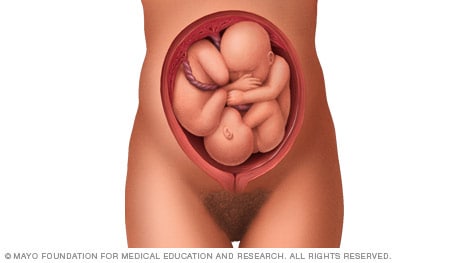

Twins

If you’re pregnant with twins and only the twin that’s lower in the uterus is head down, as shown below, your health care provider may first deliver that baby vaginally.

Then, in some cases, your health care team may suggest delivering the second twin in the breech position. Or they may try to move the second twin into a head-down position. This is done using a procedure called external cephalic version. External cephalic version involves one or two members of the health care team putting pressure on your belly with their hands to get the baby to roll into a head-down position.

Your health care team may suggest delivery by C-section for the second twin if:

- An attempt to deliver the baby in the breech position is not successful.

- You do not want to try to have the baby delivered vaginally in the breech position.

- An attempt to move the baby into a head-down position is not successful.

- You do not want to try to move the baby to a head-down position.

In some cases, your health care team may advise that you have both twins delivered by C-section. That might happen if the lower twin is not head down, the second twin has low or high birth weight as compared to the first twin, or if preterm labor starts.